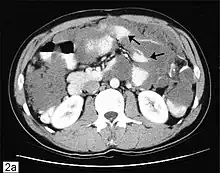

A very large ovarian cancer as seen on CT

Diagnosis of ovarian cancer starts with a physical examination (including a pelvic examination), a blood test (for CA-125 and sometimes other markers), and transvaginal ultrasound.[26][56] Sometimes a rectovaginal examination is used to help plan a surgery.[29] The diagnosis must be confirmed with surgery to inspect the abdominal cavity, take biopsies (tissue samples for microscopic analysis), and look for cancer cells in the abdominal fluid. This helps to determine if an ovarian mass is benign or malignant.[26]

CT scanning is preferred to assess the extent of the tumor in the abdominopelvic cavity, though magnetic resonance imaging can also be used.[28] CT scanning can also be useful for finding omental caking or differentiating fluid from solid tumor in the abdomen, especially in low malignant potential tumors. However, it may not detect smaller tumors. Sometimes, a chest x-ray is used to detect metastases in the chest or pleural effusion. Another test for metastatic disease, though it is infrequently used, is a barium enema, which can show if the rectosigmoid colon is involved in the disease. Positron emission tomography, bone scans, and paracentesis are of limited use; in fact, paracentesis can cause metastases to form at the needle insertion site and may not provide useful results.[29] However, paracentesis can be used in cases where there is no pelvic mass and ascites is still present.[29] A physician suspecting ovarian cancer may also perform mammography or an endometrial biopsy (in the case of abnormal bleeding) to assess the possibility of breast malignancies and endometrial malignancy, respectively. Vaginal ultrasonography is often the first-line imaging study performed when an adnexal mass is found. Several characteristics of an adnexal mass indicate ovarian malignancy; they usually are solid, irregular, multilocular, and/or large; and they typically have papillary features, central vessels, and/or irregular internal septations.[31] However, SCST has no definitive characteristics on radiographic study.[33]